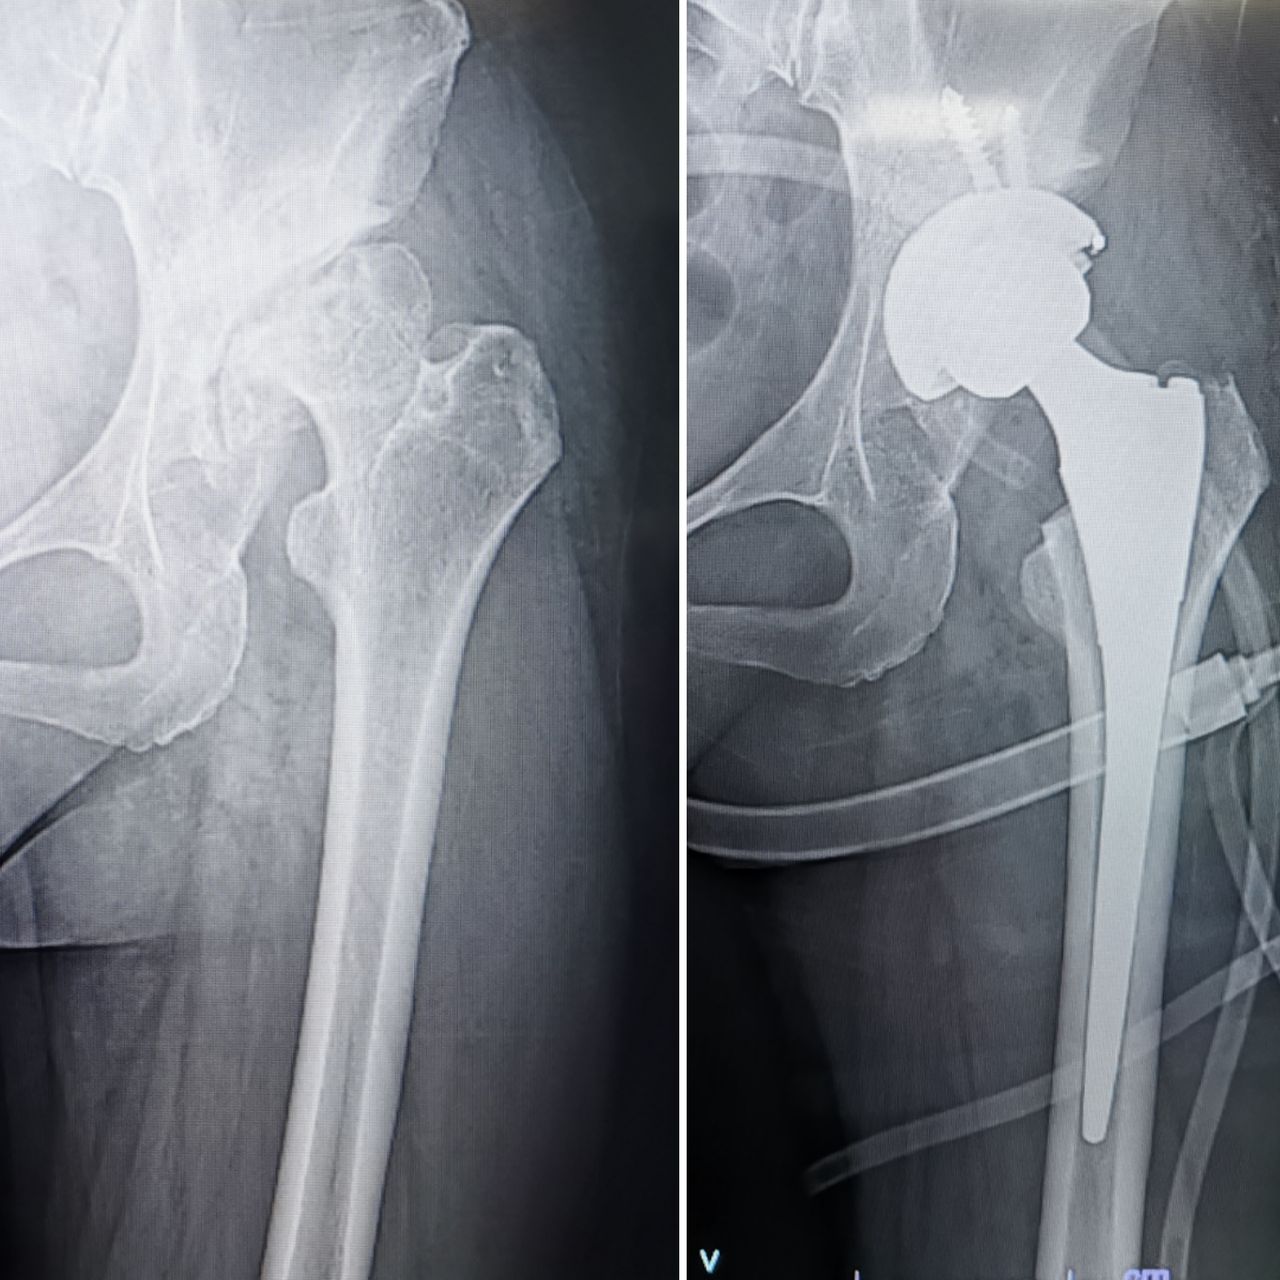

2. ALTA ESPECIALIDAD EN REEMPLAZOS ARTICULARES (PROTESIS DE CADERA, RODILLA Y HOMBRO)

• Reemplazo articular de cadera